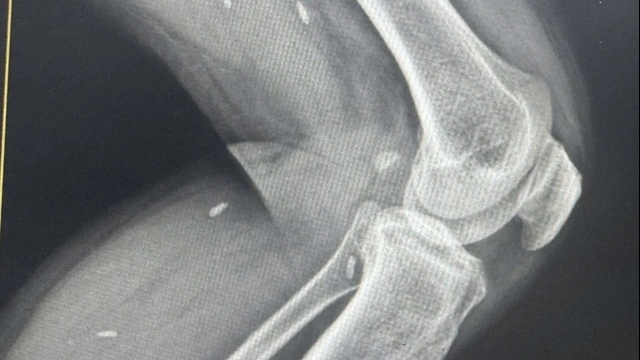

| Bệnh nhân H đã được xuất viện sau 1 tháng được ghép tim (Ảnh: BVCC) |

Năm 2021, bệnh nhân L.A.H được chẩn đoán mắc bệnh tim. Chức năng co bóp của cơ tim chỉ còn 18%. Do dịch COVID-19 nên anh chỉ có thể điều trị từ xa.

PGS.TS.BS Nguyễn Hoàng Định chia sẻ: “Bệnh nhân L.A.H được chẩn đoán mắc bệnh cơ tim giãn, chức năng tim rất kém. Nếu bệnh nhân không ghép tim kịp thời sẽ không sống được bao lâu nữa. Người bệnh đã đăng ký vào danh sách chờ của Trung tâm Điều phối tạng Quốc gia”.

Ca phẫu thuật kéo dài 5 tiếng đồng hồ, kết thúc vào 3 giờ sáng ngày 25/8. Trái tim của nam thanh niên 32 tuổi chết não do tai nạn giao thông đã đập trong lồng ngực bệnh nhân H.